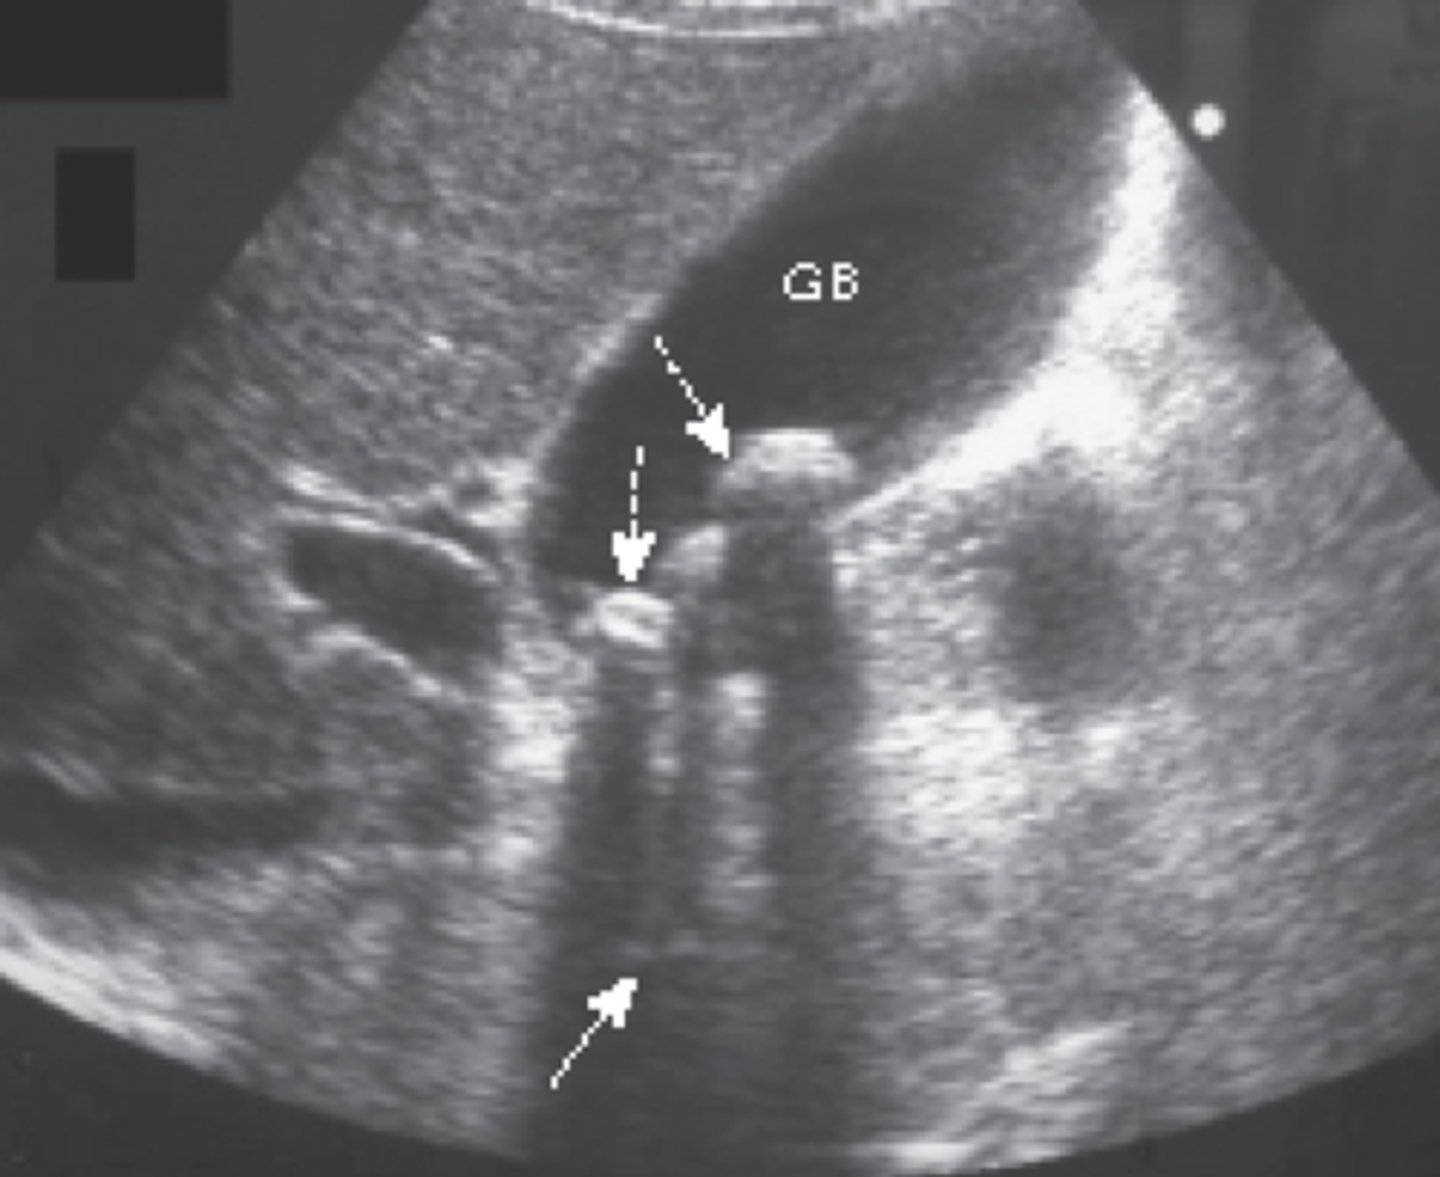

study of choice for abnormalities of biliary system

gallbladder US

gallstones

findings of acute cholecystitis

presence of gallstone (neck), thickening of gallbladder wall, fluid around gallbladder, positive murphy's sign

acute cholecystitis

hyperechoic shadowing of gallbladder walls (porcelain gallbladder)